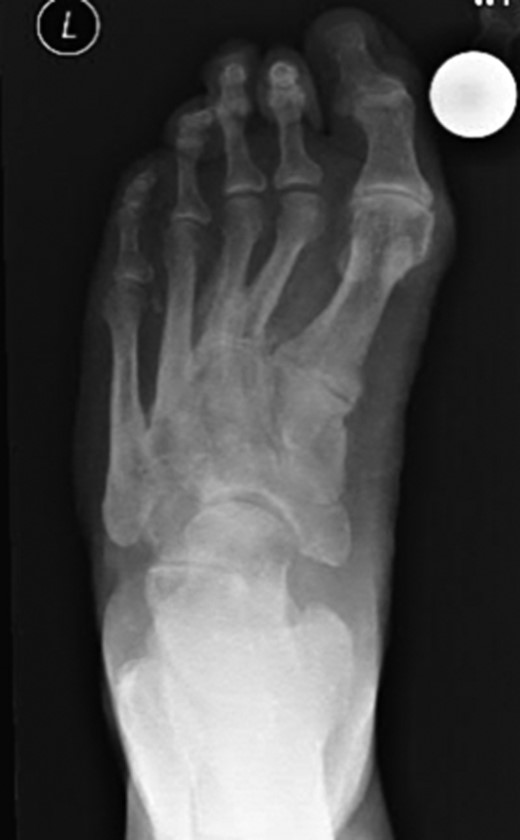

Dorsoplanter, lateral and oblique radiographs demonstrated an additional bone immediately distal to the middle cuneiform articulating with the second metatarsal base and middle cuneiform. Second and third metatarsals were shorßt in comparison with normal (Figs 1–3). Osteoarthritis was seen in all TMTJs and the first MTPJ. A computed tomography (CT) scan confirmed the presence of the additional bone and degenerative joint disease (Figs 4 and 5).

Oblique radiograph of the left foot with the clearly visible additional middle cuneiform.